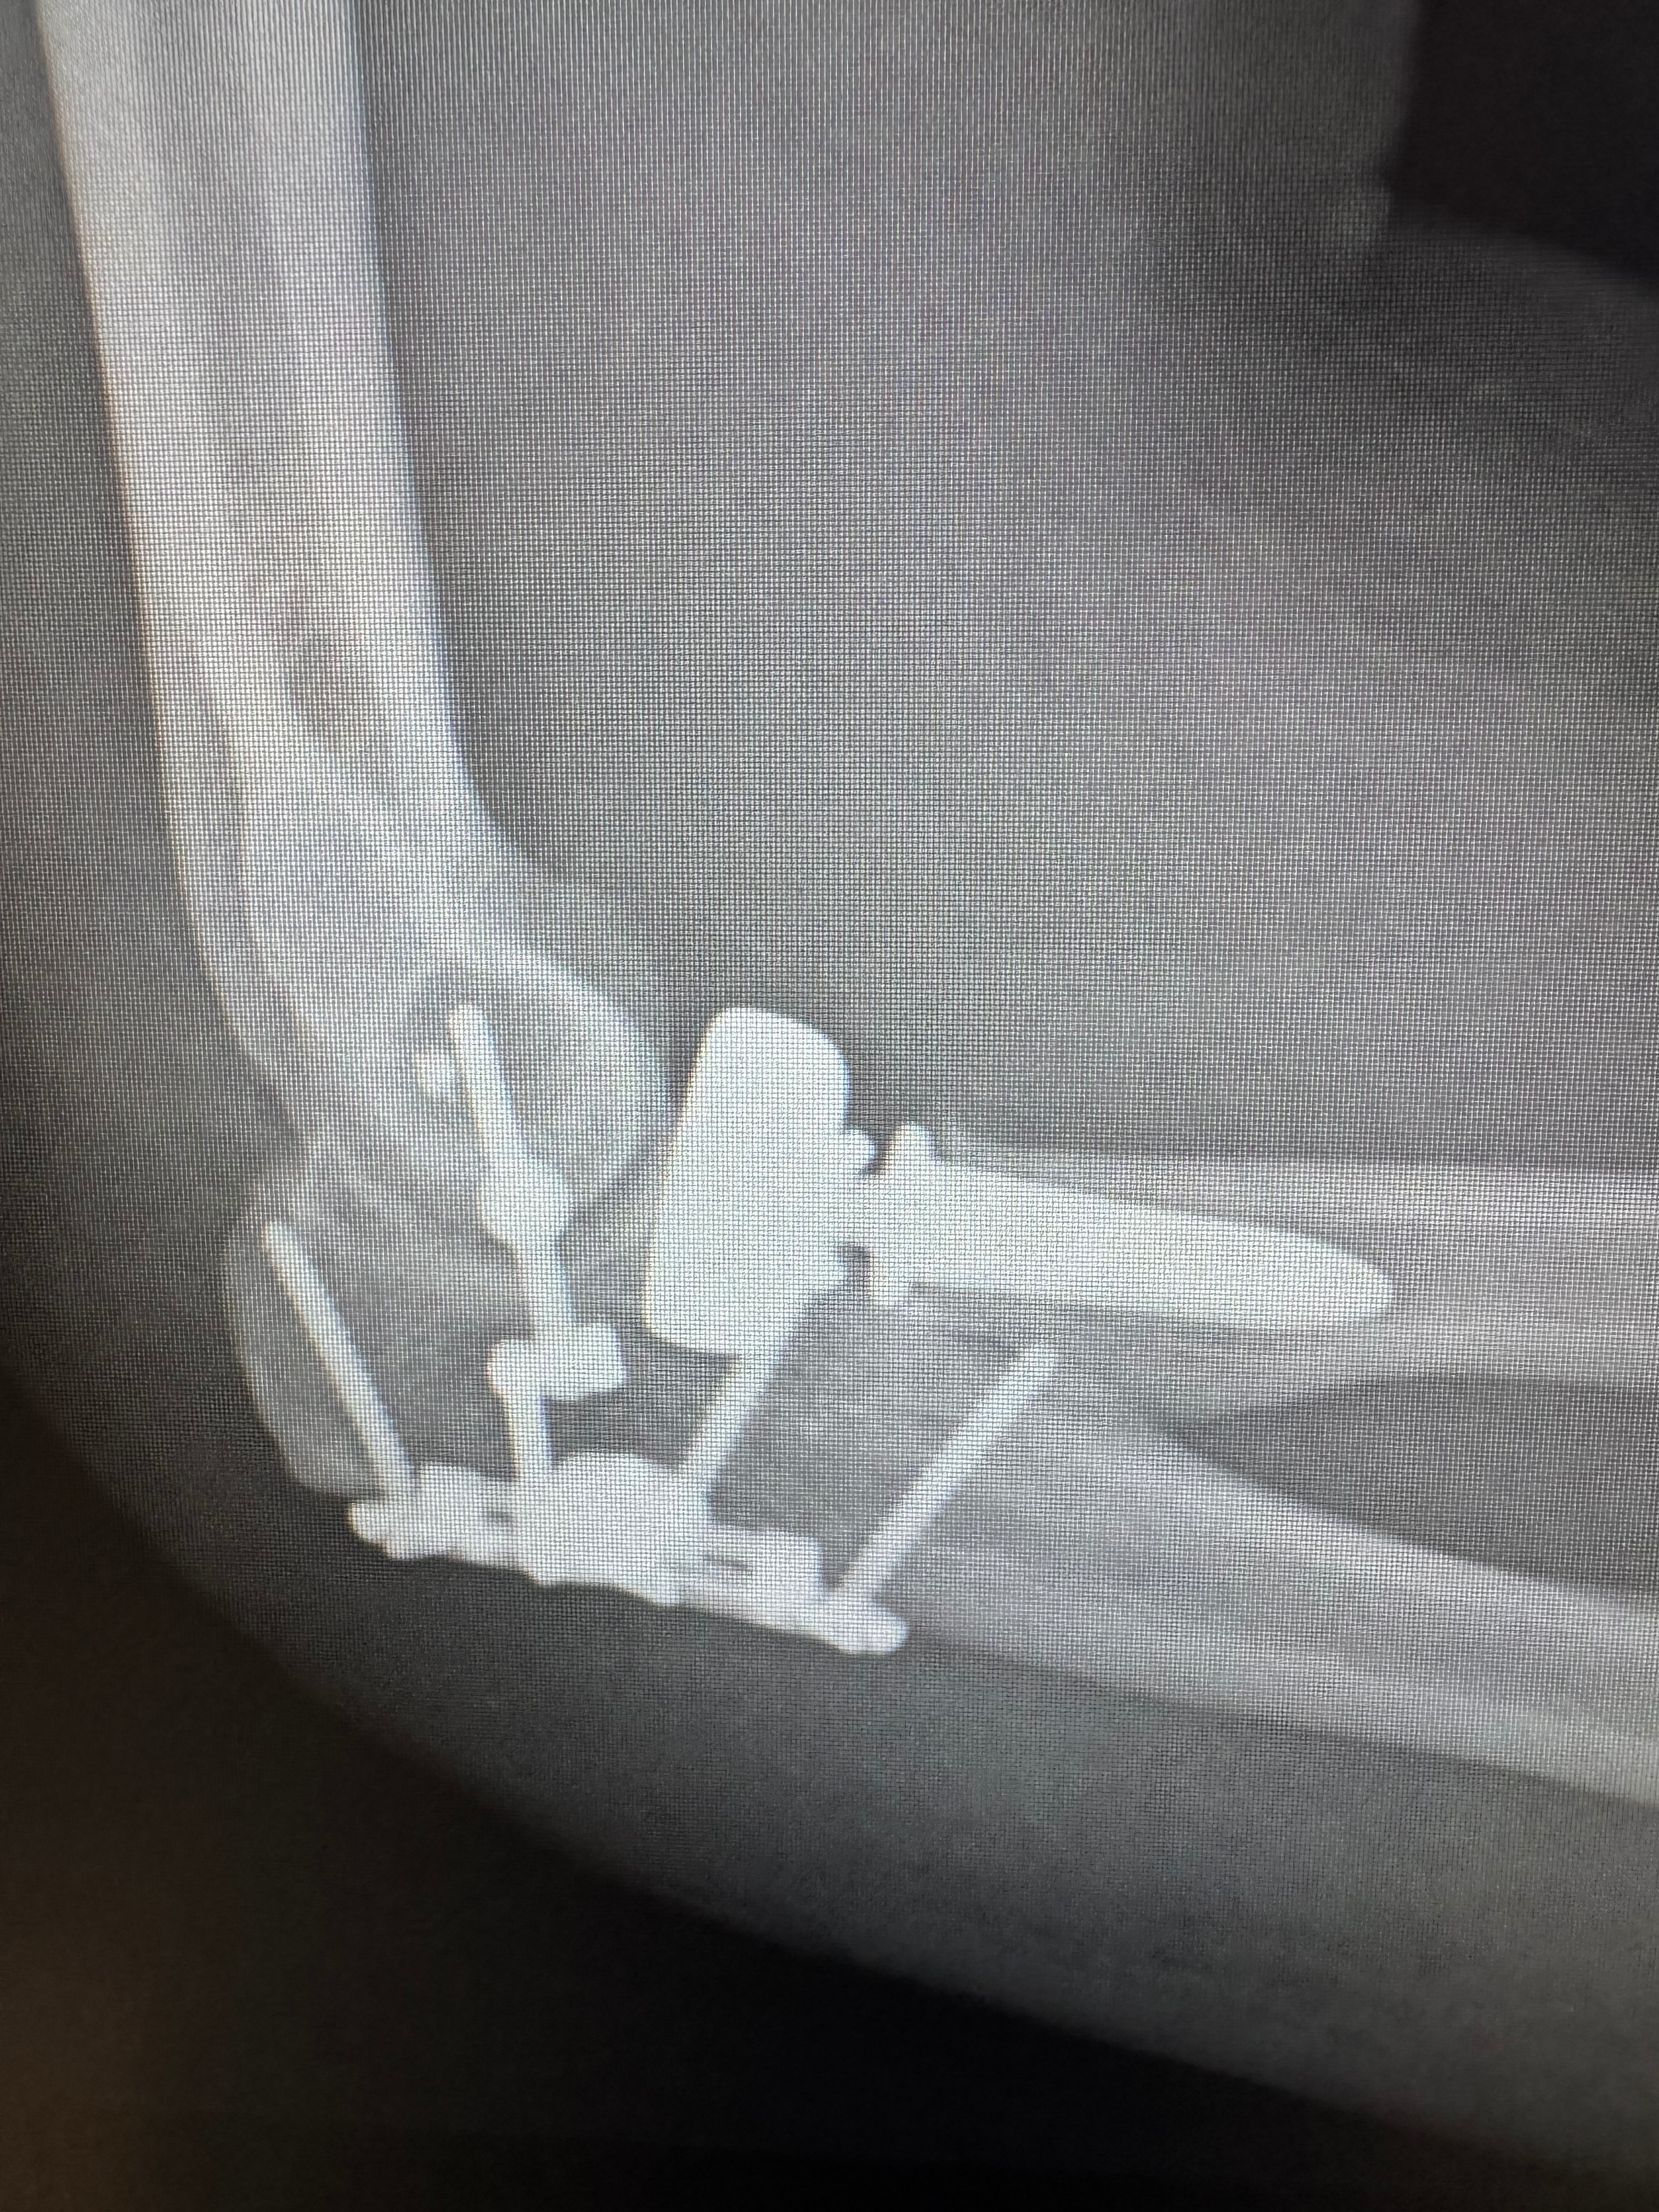

My name is James, and I’m reaching out during one of the most challenging times of my life. About a month ago, I fell off a ladder and suffered a shattered elbow and a fractured skull. Two weeks ago, I had surgery on my elbow, but now I’m back in the hospital due to an infection from the surgery. I need another surgery to try to rid the infection before it gets worse, and I’m facing a long road to recovery. The injuries have left me unable to work for at least the next six months, and I’m currently recovering in the hospital. On top of this, I’m expecting the birth of my son in just three months, which should be a time of joy and excitement, but instead, I’m overwhelmed with worry about how I’ll provide for him and keep up with my bills while I heal.